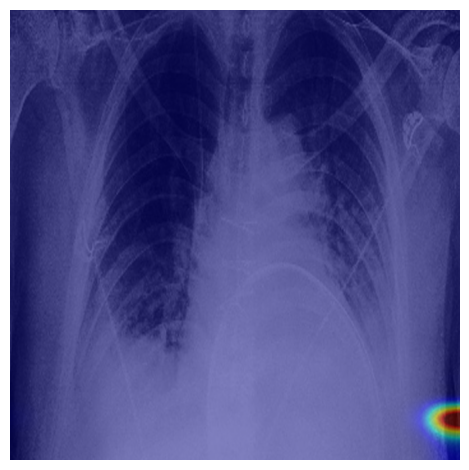

Refer to caption

(a) Healthy(1)

(b) NODE21

(c) Healthy(2)

(d) VinDr-CXR

Figure 5: Grad-CAM-based saliency maps illustrating model interpretability across datasets. Top row: Examples from NODE21 showing baseline (a) and curriculum-trained (b) models. Bottom row: Examples from VinDr-CXR demonstrating consistent attention patterns (c, d).

Grad-CAM visualizations showed that curriculum-trained models consistently focused on anatomically meaningful lung regions near nodules (Figure 5b), while baseline models activated broader, clinically irrelevant regions (Figure 5a). Similar attention patterns were observed across NODE21 and VinDr-CXR examples (Figure 5c,d), supporting interpretability and robustness.